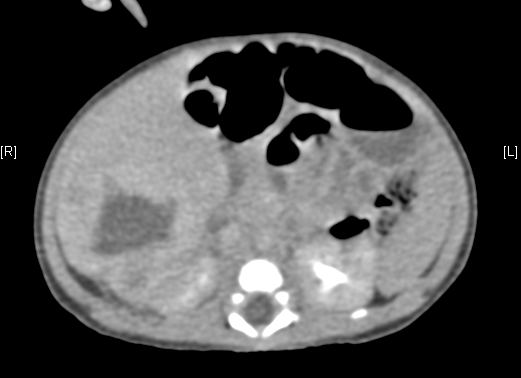

上腹部增强CT:肝脏右后叶血管源性肿瘤可能性大。上腹部增强CT:肝脏右后叶血管瘤可能性大。

术前CT检查:

动脉期

静脉期

平衡期